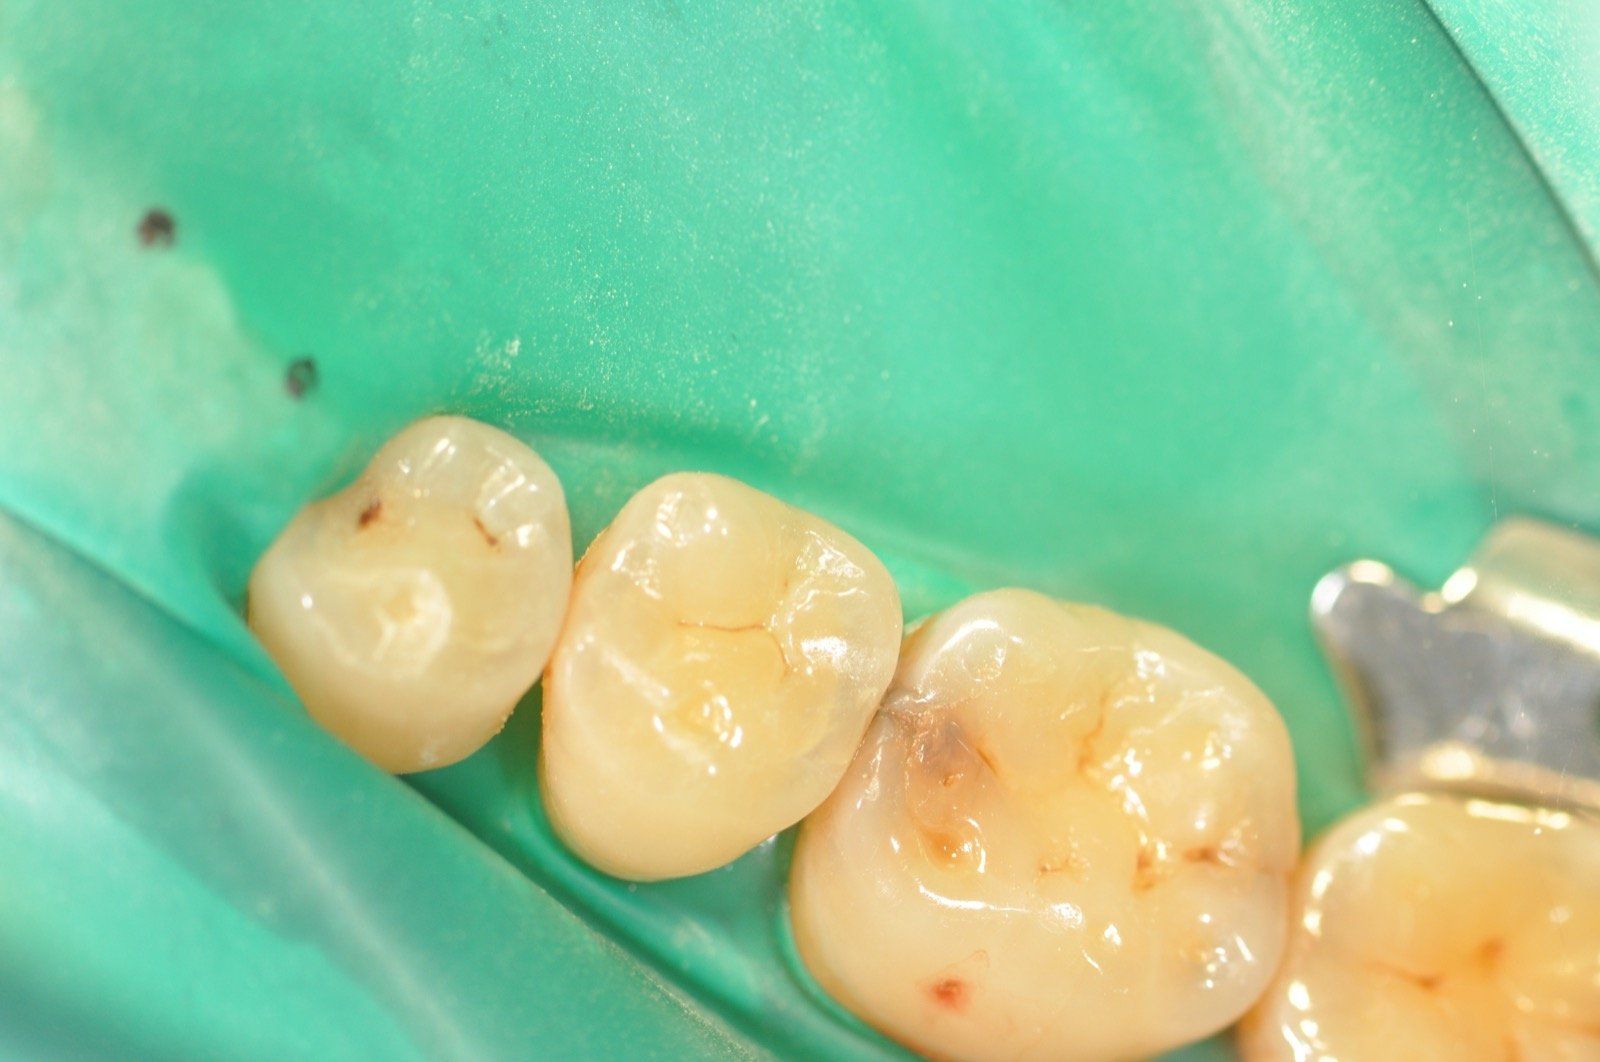

Odontoiatria conservativa

La conservativa è una branca dell'odontoiatria restaurativa che ha come scopo quello di “conservare” l’elemento dentario. Ciò significa che si cercherà, in un dente non eccessivamente compromesso, di evitare la devitalizzazione ove possibile e di restaurare il dente secondo protocolli rigidi che ci garantiscano una longevità della ricostruzione.

Andremo ad effettuare il restauro del dente nella sola parte compromessa dalla carie salvaguardando la sostanza biologica residua, da noi giudicata sana, in modo tale da garantire una ricostruzione di qualità.